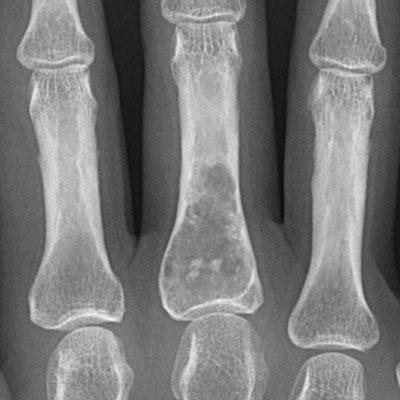

El encondroma es bastante común en los huesos pequeños de las manos y pies, con 58% (ochenta y nueve de 153) de las lesiones que ocurre en estas áreas. De hecho, el encondroma es el tumor primario más común encontrado en los huesos de la mano. El encondroma asintomático normalmente se encuentra, incidentalmente, en las radiografías. El encondroma atípico se caracteriza así debido a su asociación con una historia de dolor. A veces se ve una fractura en el área del encondroma, quizás debido a debilitad previa del hueso o simplemente como un hallazgo incidental.

El encondroma es una lesión larga, oval que se localiza centralmente en la porción tubular del hueso. Normalmente tiene groseramente y típicamente una apariencia lobulada y bien delimitada (los lóbulos son de tamaños diferentes y separados por septos pequeños de tejido fibroso). La calcificación de la lesión puede o no estar presente. La expansión de la corteza circundante es rara a menos que la lesión ocurre en un hueso pequeño, como los huesos de las manos o pies, o en el peroné.

Las radiografías de la en condromatosis de las manos y los pies son características. Se ven masas radiolucentes de cartílago con focos de calcificación, parecidos a los de los encondromas solitarios, que deforman severamente los huesos. Los encondromas en esta localización pueden ser intracorticales y periosteales. Algunas veces sobresalen de la diáfisis de los huesos cortos o largos, y asemejan a los osteocondromas. Pero estas proporciones nunca poseen una cubierta cartilaginosa de un tallo óseo. En los huesos largos se ven bandas radiolucentes que se extienden desde el platillo decrecimiento hasta la diáfisis. La coalescencia de encondromas metafisarios, a menudo provoca un agrandamiento asimétrico de los huesos largos.